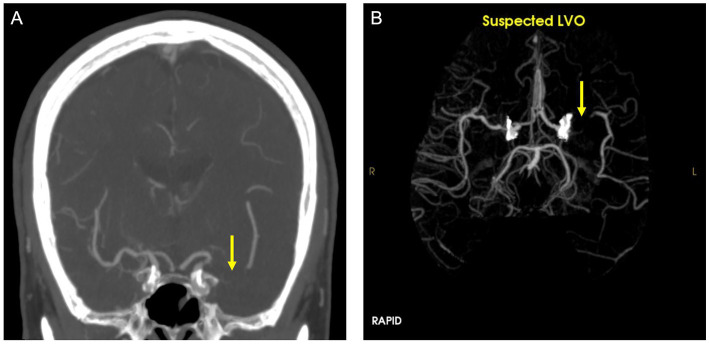

Two grayscale images, one showing a brain with a yellow arrow, another showing a vascular network with a yellow arrow

A 2023 study from researchers at UC Irvine's Center for Artificial Intelligence in Diagnostic Medicine investigated whether AI-powered image recognition software could help doctors speed up stroke diagnoses. The yellow arrow in both images points to a blocked vessel (large vessel occlusion, or LVO) in the brain; A) shows the image analyzed by human providers, and B) shows the blockage detected by AI. "This is a true positive confirmed by ... ground truth," researchers concluded. Credit: Front Neurol. 2023; 14: 1179250.